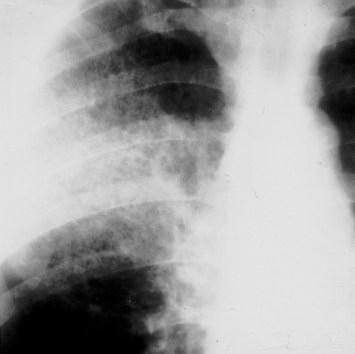

SIGNO DE LA CISURA ABOMBADA O DE LA HINCHAZÓN DEL LÓBULO

Este es un signo poco útil en la actualidad. Es visible en la radiografía de frente de tórax y se presenta como una condensación alveolar que se asocia a un abombamiento inferior de la cisura adyacente (flecha). Este signo, descrito inicialmente como característico de la neumonía por Klebsiella (neumonía de Friedlander), ha sido visto en otras entidades: neumonía por neumococo, H. influenzae, tuberculosis, absceso, neumonitis obstructiva, e incluso en el carcinoma bronquioalveolar.